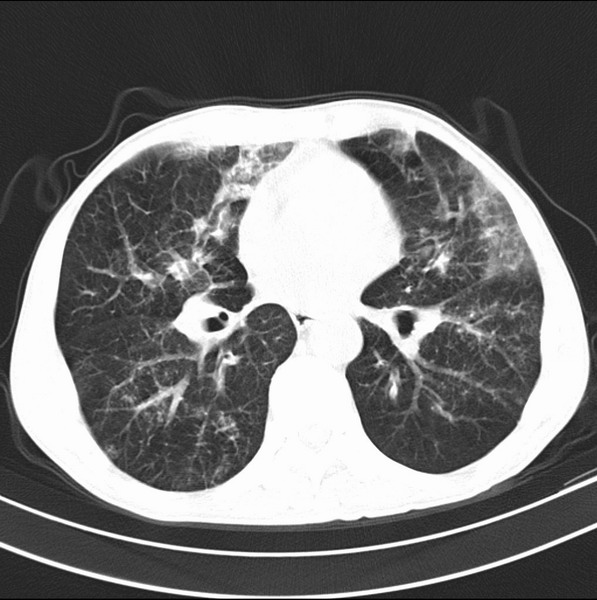

标题: CT19600:能否诊断为转移?

女、55

3年前盲肠癌、一年半前诊断膀胱癌,现在呼吸困难,临床考虑为肺转移

请问胸部ct如何诊断?能否排除淋巴管炎,纵隔窗没有问题。

考虑间质性病变,癌性淋巴管炎可能.

转移,癌性淋巴管炎。

建议抗炎后复查,不除外癌性淋巴管炎。

考虑间质性病变,癌性淋巴管炎可能.支持!

支持考虑间质性病变,癌性淋巴管炎可能.